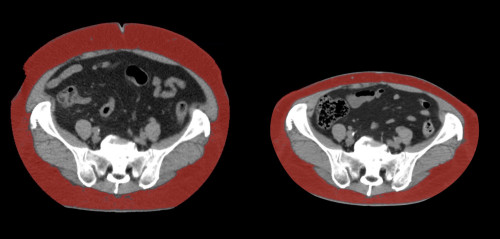

②

40代・女性(ご本人のご厚意で画像提供)

治療内容:チルゼパチド2.5mgの週1回自己注射による脂肪減少と脂肪肝改善

治療期間: 6ヶ月(26週)((用量は2.5mgから開始し最大で15mg。減量効果が得られる必要用量には個人差があります。))

費用:自由診療の場合は4400円(税込)×26(週)=114400円

想定されるリスク・副作用:下記に副作用を記載

※医療広告ガイドラインに準拠して表記

1:脂肪の減少

皮下脂肪の減少(赤色部分)